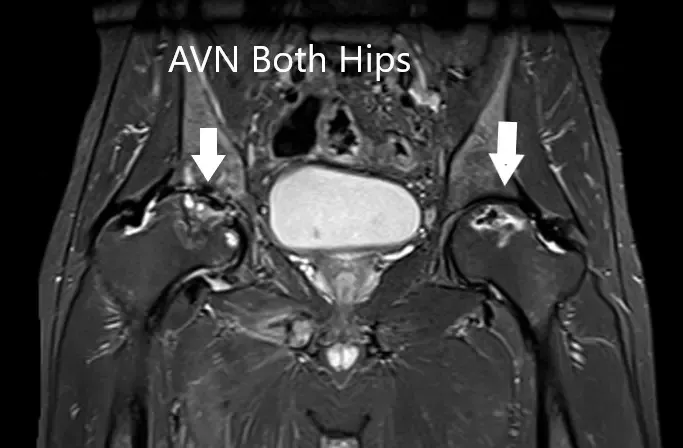

MRI suggested marked signal attenuation of bilateral femoral heads. There was a collapse of the right head and precollapse stage 2a of the left hip.

MRI showing bilateral femoral head AVN in T1WI